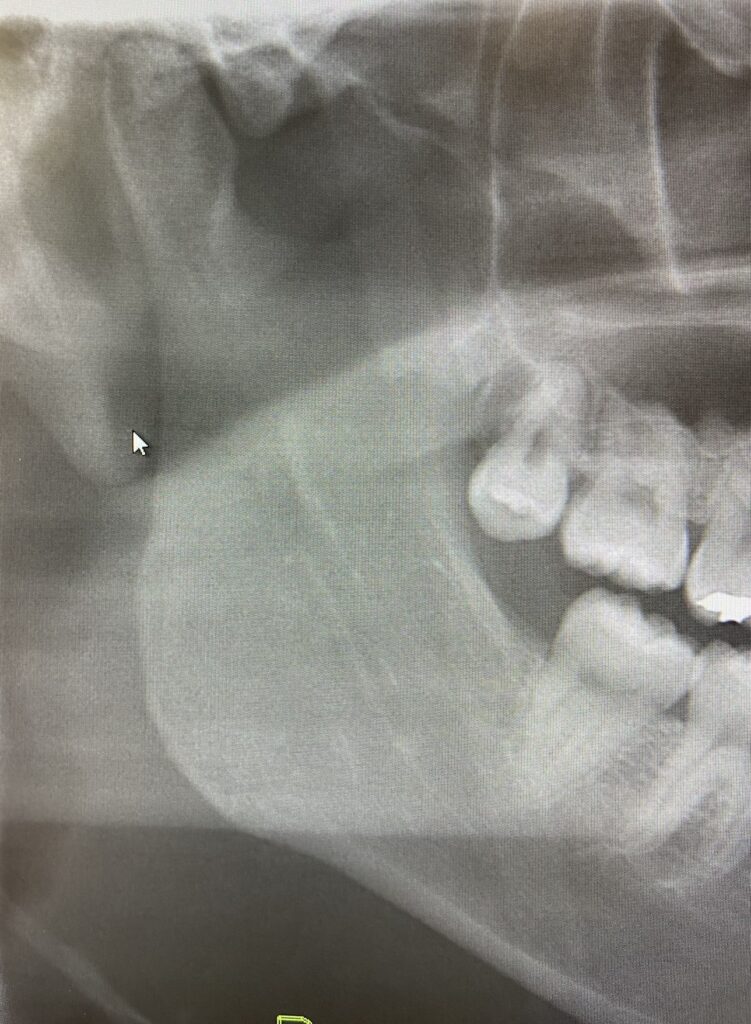

体格の良い方や顎の骨が硬い方などは骨が厚く、しっかりとしているために麻酔が効きにくいことが少なくありません。

普通の麻酔はあごの骨の中まで針は入りません。骨の表面に麻酔薬を置いておくと、徐々に骨の中に浸透してゆきます。ですから、骨の密度や、骨の表面から目標の歯までの距離などに影響を受けます。

特に下顎の奥は骨が硬く一般の方でも時として麻酔が効きにくいことがあります。

下顎の奥歯の虫歯の治療を行う際は麻酔が効きにくいことを覚えておきましょう。